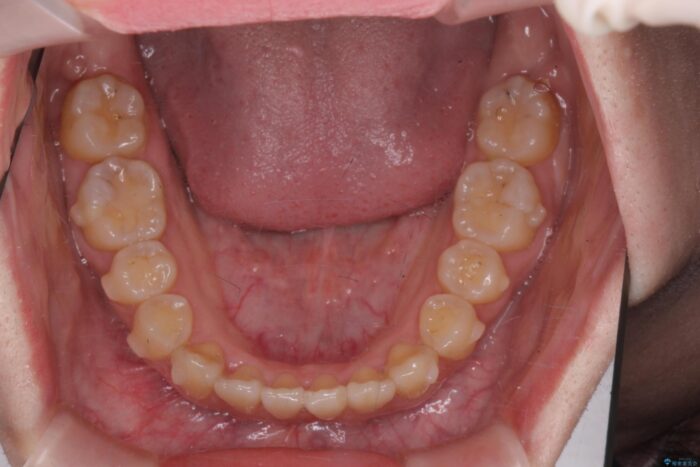

前歯のねじれが気になる、歯並びを改善したいとご来院された患者様です。

歯のねじれをきれいに取るのは、インビザライン(マウスピース矯正)だけでは難しい動きです。そのため、事前に4か月間の部分ワイヤー矯正を行い、治療期間を短くし、より美しい仕上がりを目指す計画です。